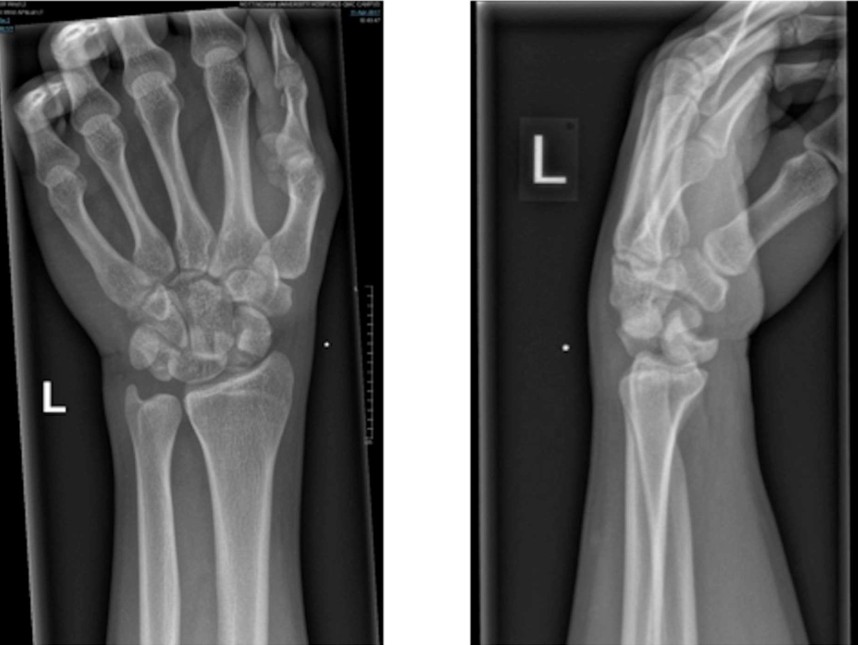

Perilunate wrist dislocation

An 88-year-old man is brought in by ambulance to your emergency department atier a fall down 3 steps onto his …

FOOSH injury

A 25-year-old man has presented to the ED after falling 2m off a balcony onto his outstretched left hand.